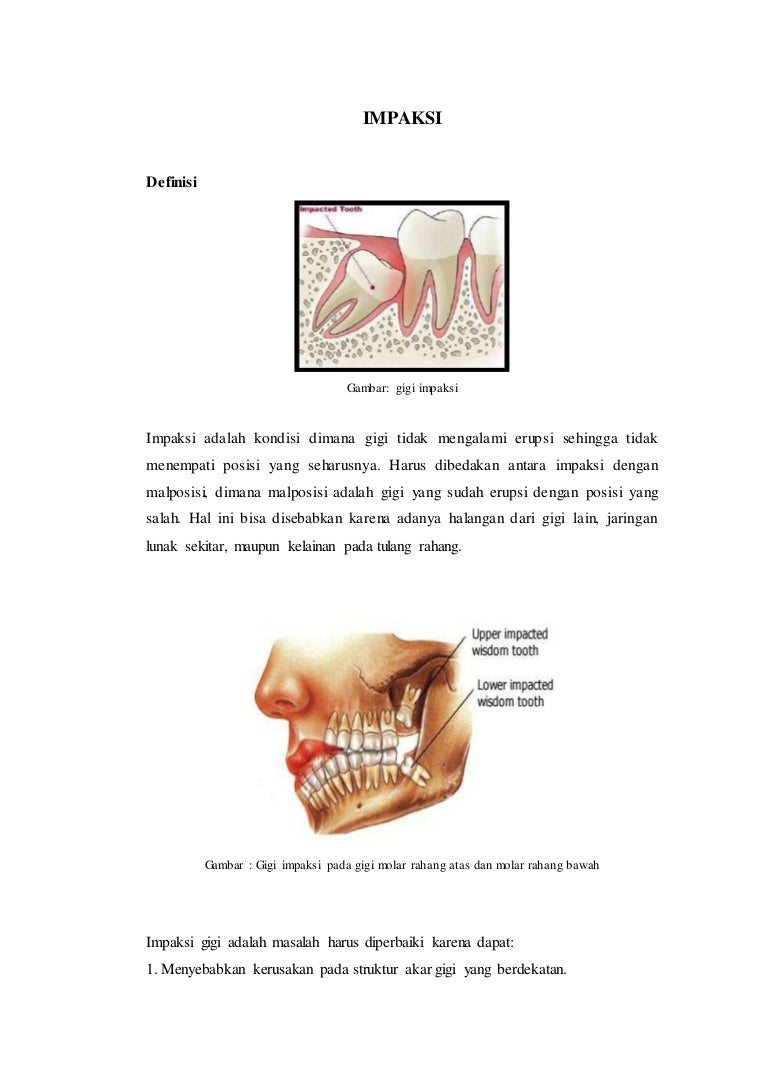

Impaksi maggie

Impaksi maggie

Apa yang dimaksud dengan impaksi gigi? - Ilmu Kedokteran Gigi - Dictio Community

Apa yang dimaksud dengan impaksi gigi? - Ilmu Kedokteran Gigi - Dictio Community

BAB 2 TINJAUAN PUSTAKA 2.1 Definisi Gigi Impaksi Gigi impaksi merupakan gigi yang tidak dapat muncul sepenuhnya ke dalam rongga